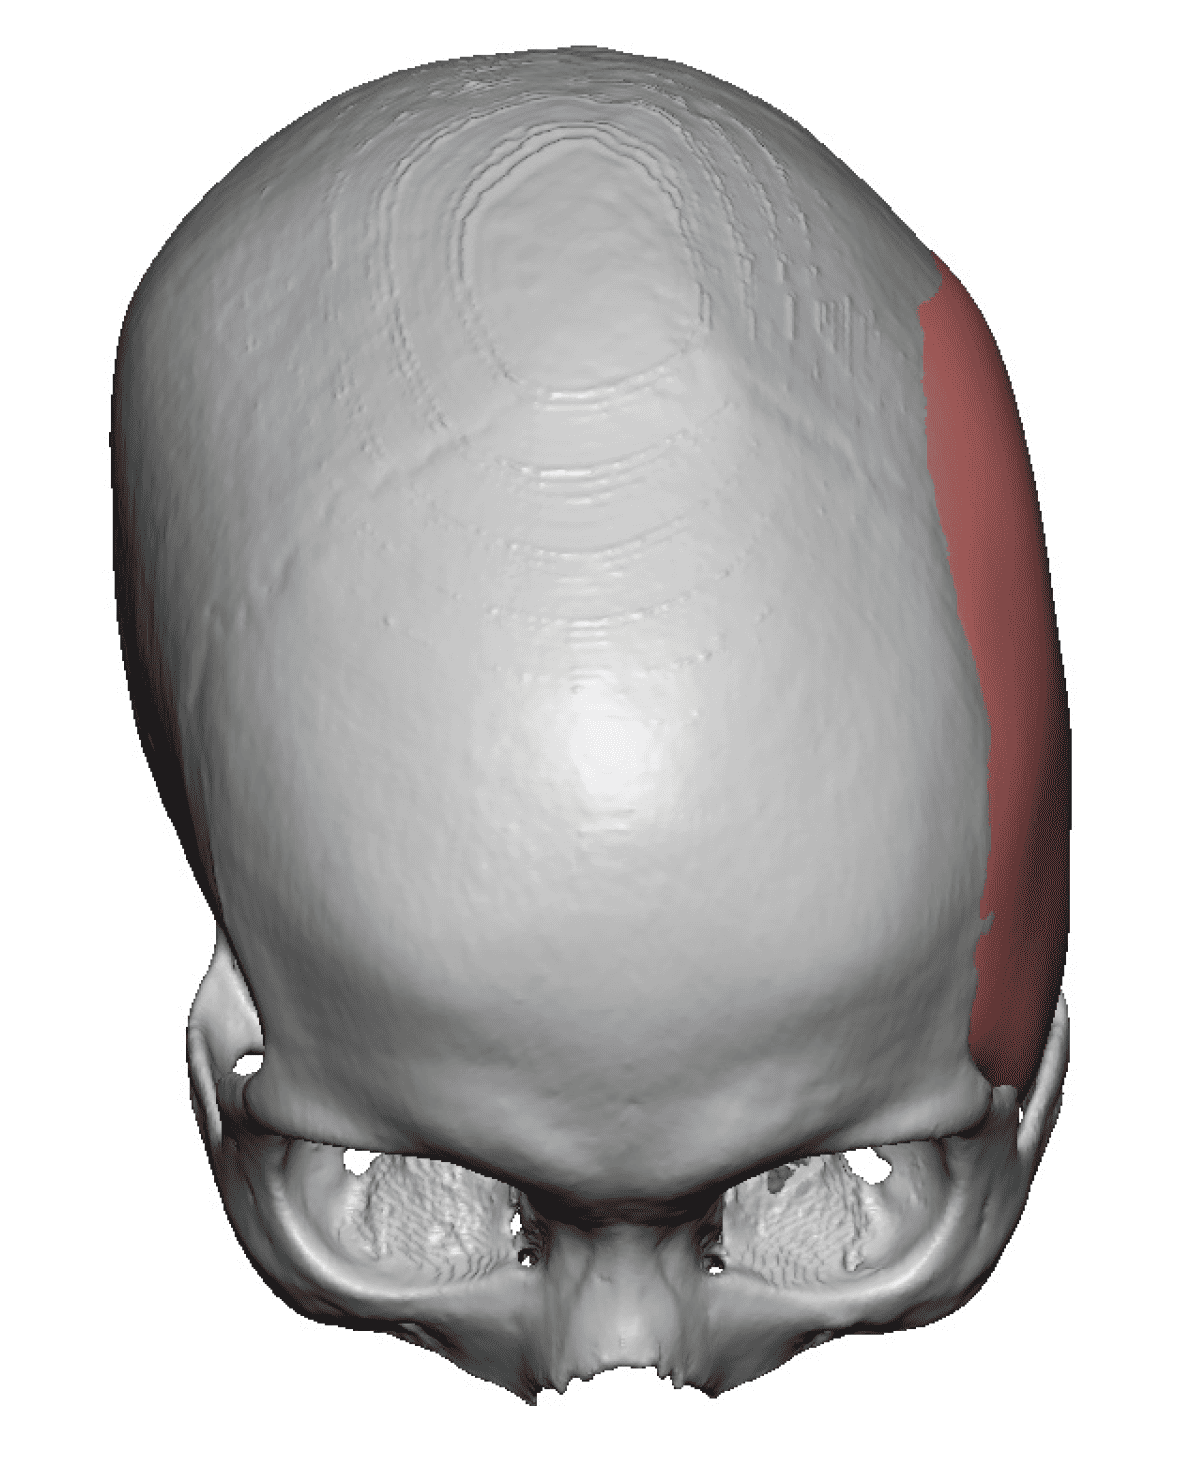

Patient 84

Desire for change of head shape from front view form an inverted V shape to a rounder and wider head shape.

Placement of custom extended forehead-temporal implants through incisions in the crease behind the ear. (he had a prior back of head skull implant which is green in the implant designs and which the head widening implants partially covered it)

Desire for change of head shape from front view form an inverted V shape to a rounder and wider head shape.

Placement of custom extended forehead-temporal implants through incisions in the crease behind the ear. (he had a prior back of head skull implant which is green in the implant designs and which the head widening implants partially covered it)